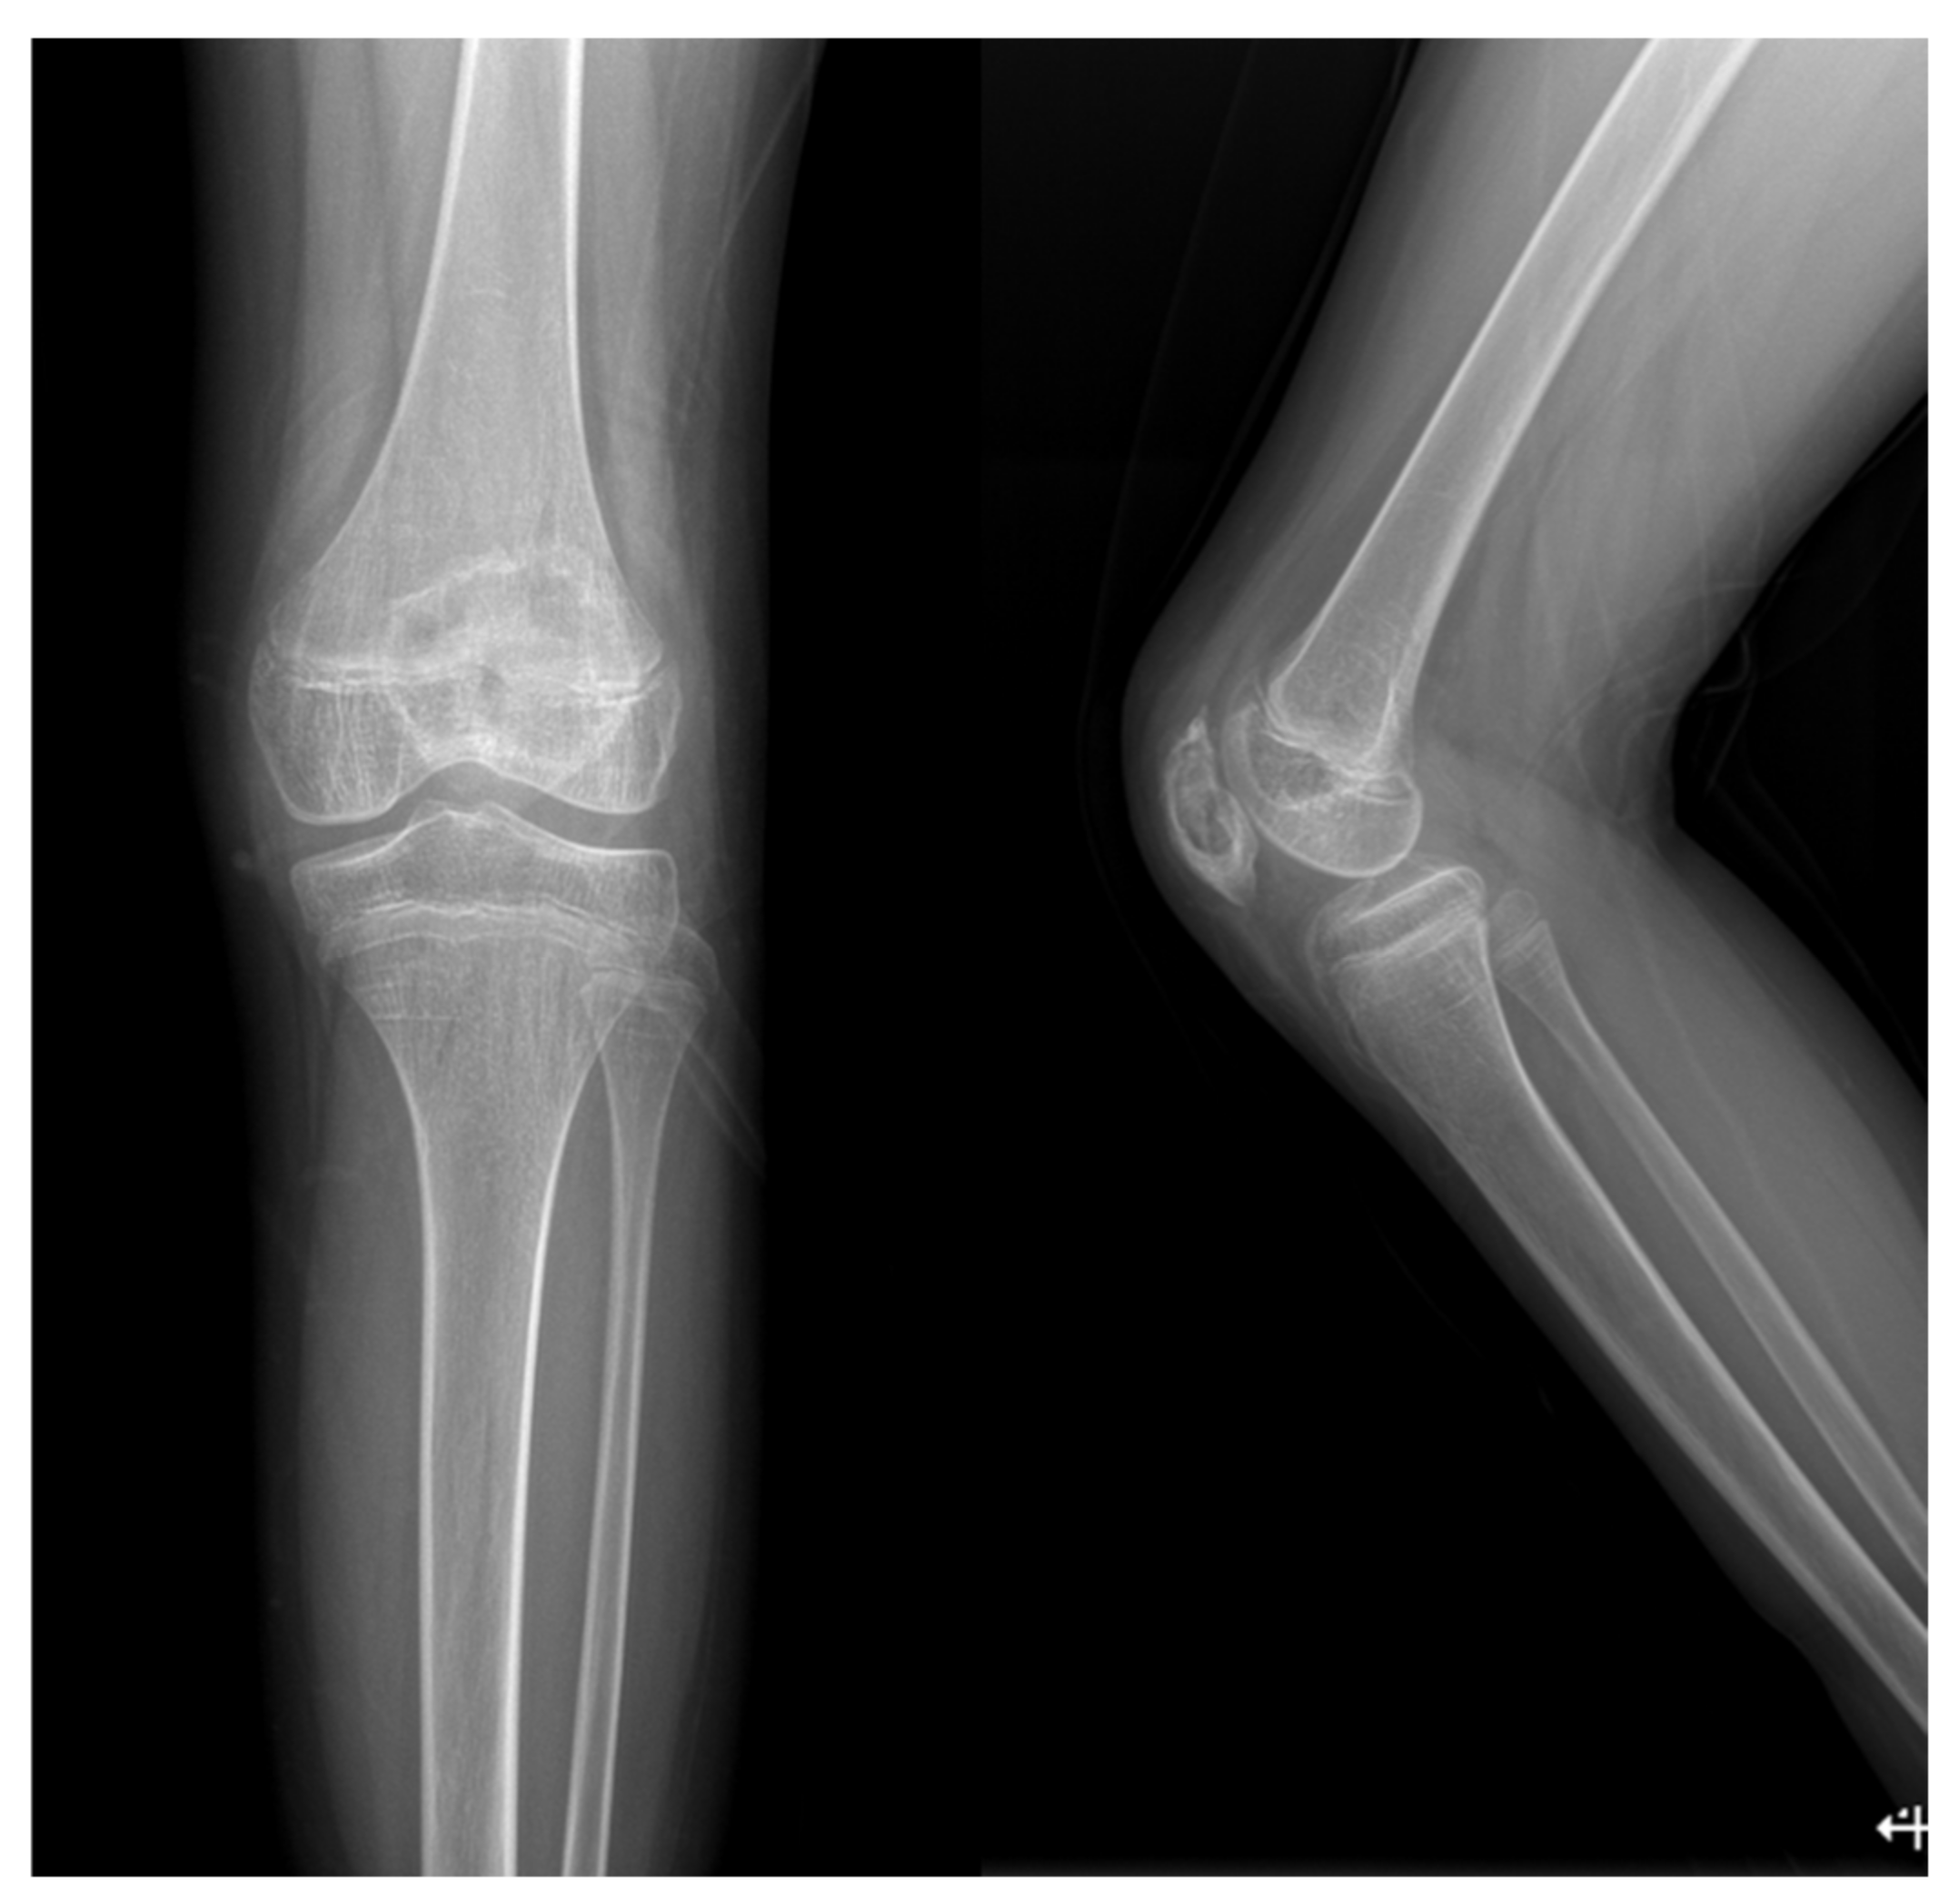

Patellar Osteomyelitis in a 9-Year-Old Patient with Chronic Granulomatous Disease: A Case Report

2. Case Report